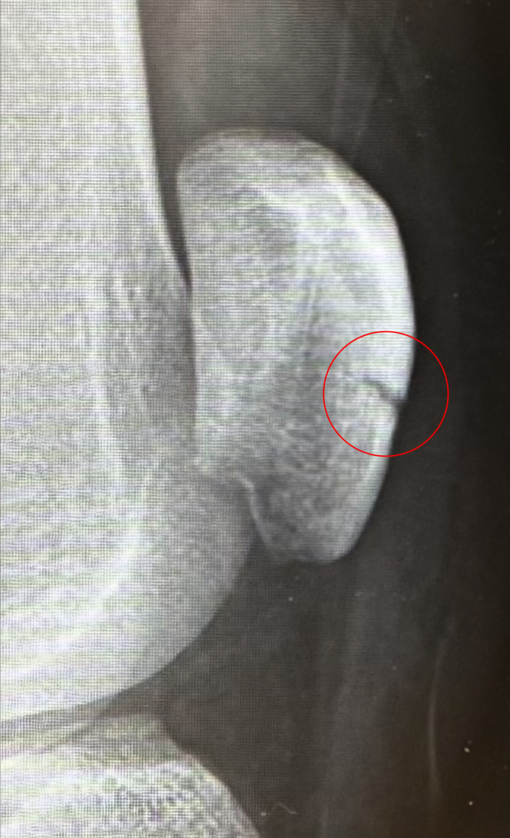

膝の骨折から2週間。

経過観察でレントゲンを撮りにいって、経過は順調。

ようやく少しずつ痛みが引いてきて、今日から「曲げる練習」もスタート。

まだ先は長そうだけど、一歩ずつ進むしかないので焦らず頑張ります!!